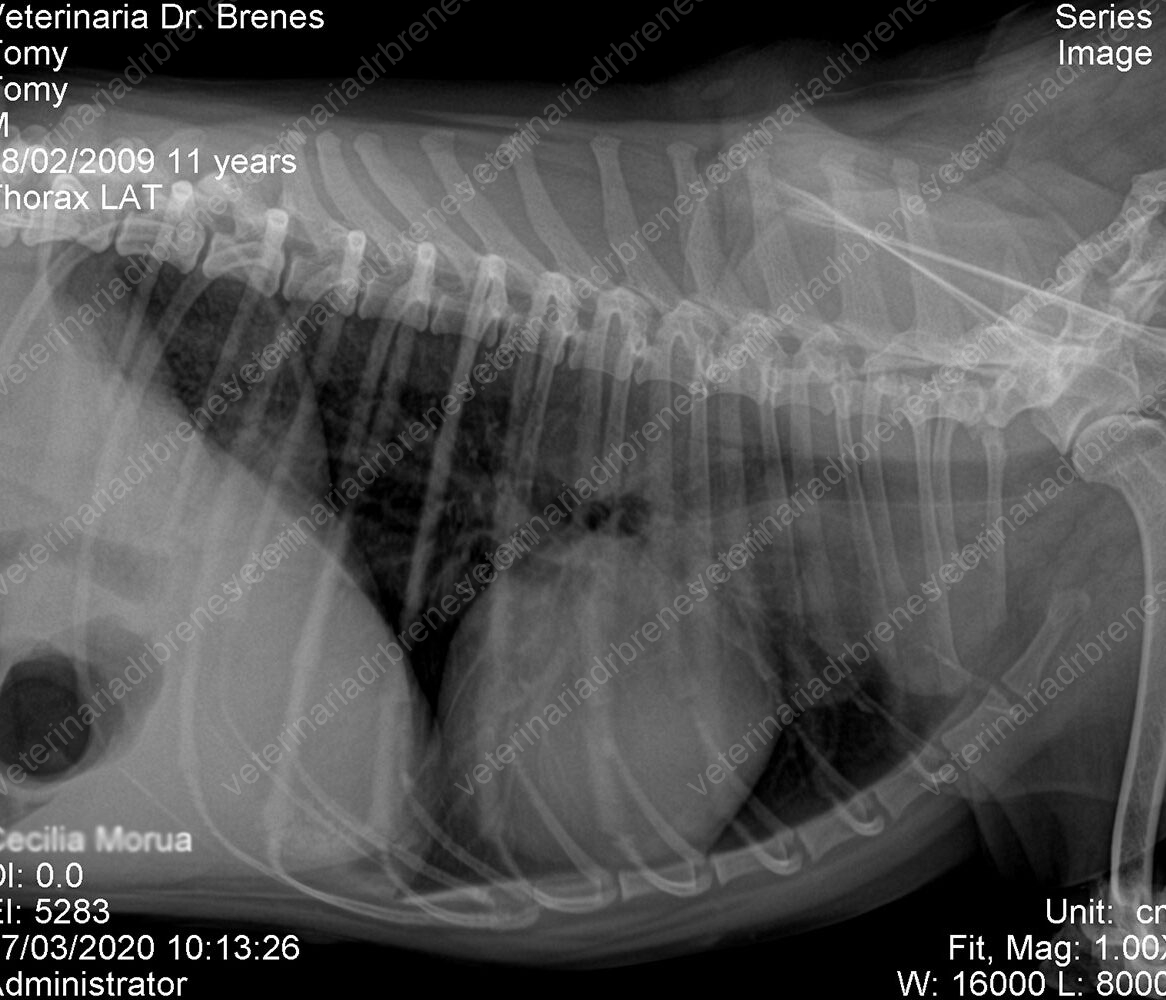

Los estudios radiológicos son métodos complementarios no invasivos que nos ayudan a valorar a nuestros pacientes. Los Rayos X los utilizamos para poder observar la integridad de los huesos en caso de sospecha de fracturas. Modificando la técnica radiológica podemos observar estructuras blandas como ciertos órganos: corazón, pulmón, hígado, bazo, vejiga, riñones etc. Cuando sospechamos de cuerpos extraños en el estómago o intestino, se realizan radiografías con medio de contraste, el cual nos permitir visualizar el pasaje intestinal, así como cuerpos extraños que retenga el medio de contraste como por ejemplo telas, papel u otros materiales que puedan contener el medio de contraste.